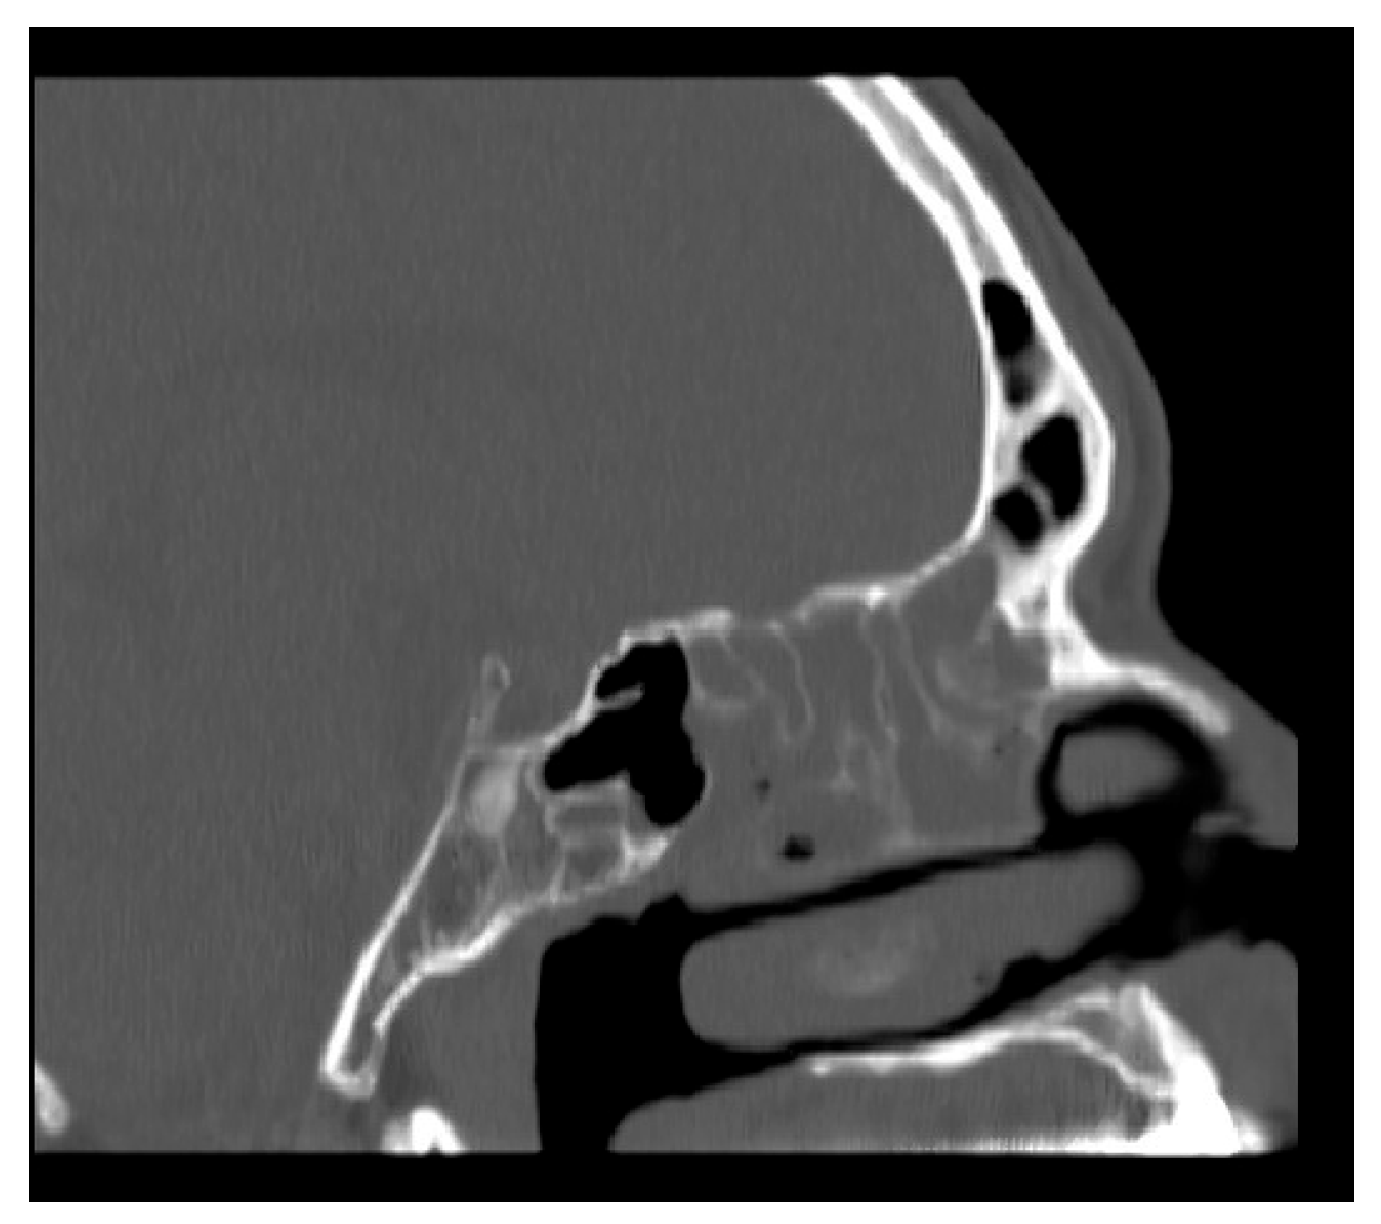

2.1. Method of NasoLens Safety and Effectiveness Simulation

We aimed to assess NasoLens’ ability to safely and effectively navigate the nasal canal without causing injury or discomfort. To simulate the nasal anatomy, a range of CT scans was obtained from a hospital. These scans were selected to capture various anatomical variations and ensure that the test models represented a diverse patient population, as shown in Figure 1. Using these scans, accurate 3D digital models of the nasal passages were generated, as shown in Figure 2. The digital models were subsequently converted into physical representations using 3D printing technology, allowing us to evaluate NasoLens’ ability to reach key target locations.

Figure 1. CT scan of nasopharynx.